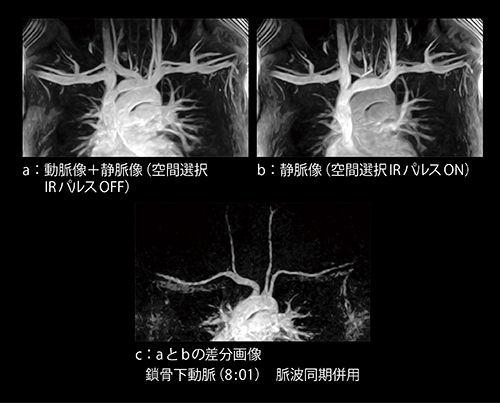

図5に差分法で取得した鎖骨下動脈の画像を示します。図5 aは空間選択IRパルスをOFFで取得した動脈像+静脈像,図5 bは空間選択IRパルスをONで取得した静脈像です。そして,図5のaとbを差分した画像がcの動脈像となります。

3心拍ごとに心拡張期で撮像を行っているため,十分に血液が回復でき,良好に鎖骨下動脈が描出できています。オープンMRIは,高磁場装置と比べると磁化率の影響を受けにくいという特長もあります。そのため,鎖骨下動脈付近で発生しやすいバンディングアーチファクトは,高磁場装置と比較すると少なくなります。オープンMRIの開放性を生かして,腕を外転させた状態でも撮像することが可能です。

図5 VASC-ASLの差分法における鎖骨下動脈の画像